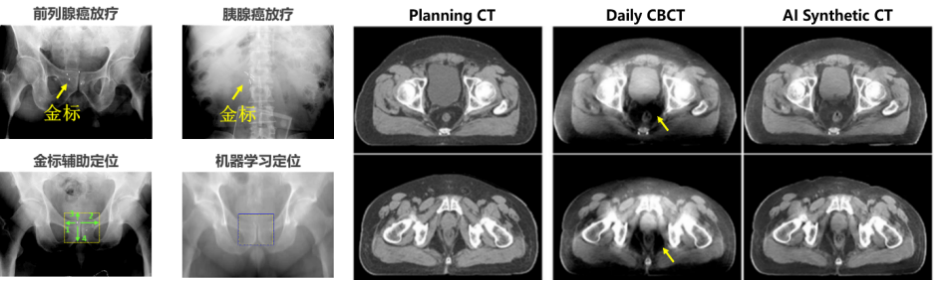

l 圖像引導放射治療